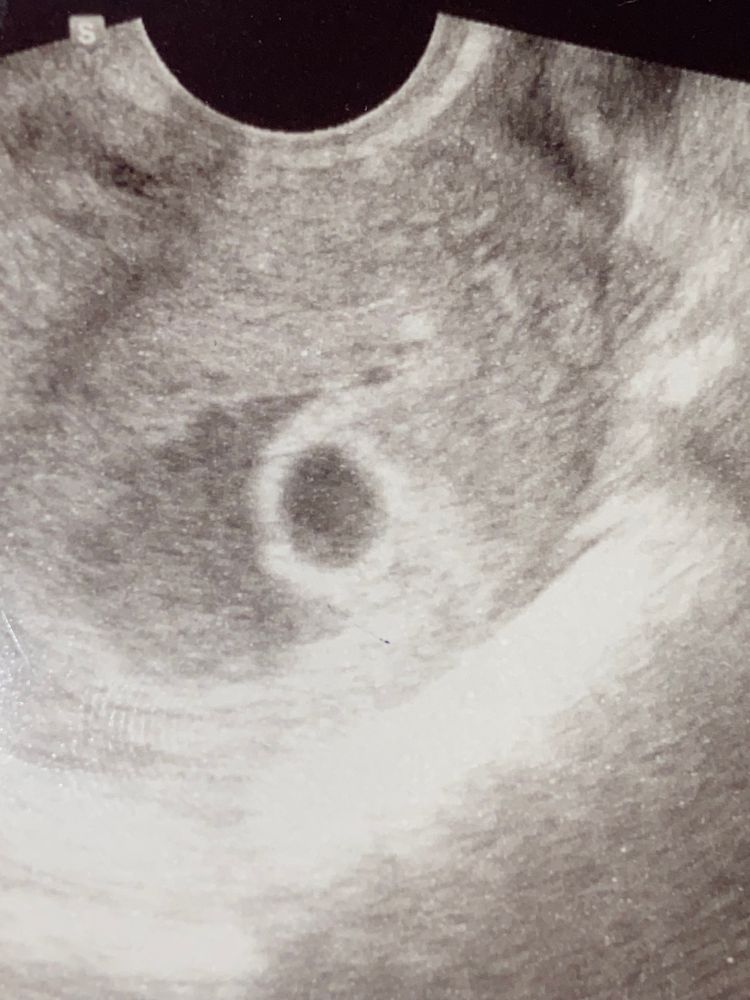

Эмбрион, желточный мешочек?

Девочки сходила на узи, написали желточный мешочек и эмбрион не визуализируются , сейчас присмотрелась и что то вижу ?! Оно или это блики узи 🤷♀️

Возможно просто кратинка такая на узи, т. К. Обычно плодное яйцо внутри гораздо темнее. Может быть очертания будущего жм. Смущает такая область темноватая возле пя, полумесяцем. У меня так гематома выглядела.

у меня такая картинка была, но увы-анэмбриония.... У вас какой срок? Может еще рано?

Есть какая-то тень небольшая. Какого размера у вас плодное яйцо? Может еще рано просто)

Елена , рано пошли, желточный мешочек должен появиться до 13 мм, эмбрион до 25 мм, сердцебиение до ктр 4-6 мм. Попробуйте через неделю-две сходить, будет скорее всего уже эмбрион, а через 2 и сердечко.